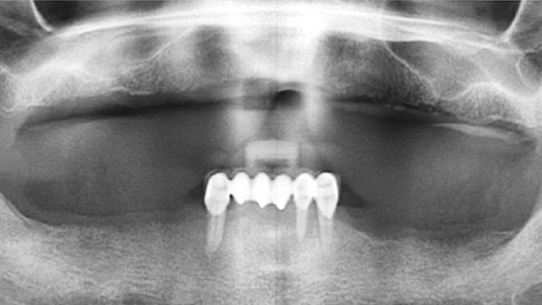

상악틀니를 사용 중 저작력이 약한 환자분. 대학병원에서 전체 임플란트를 받으시려 했으나 비용 문제로 고운미소로 내원하셨습니다.

당뇨수치가 있어 내과와 연계하여 식생활 조절과, 운동, 인슐린 치료를 병행하여 충분한 혈당관리를 하고

임플란트 수술을 시행하였습니다.

임플란트를 지지하기 위한 뼈의 상태가 좋지 않아, 상악동 뼈 이식과 함께 총 24개의 임플란트를 식립하였습니다.

전체 임플란트가 완성된 이후에도 내과와 지속적인 연계로 전신건강이 회복될 수 있게 노력해야 합니다.